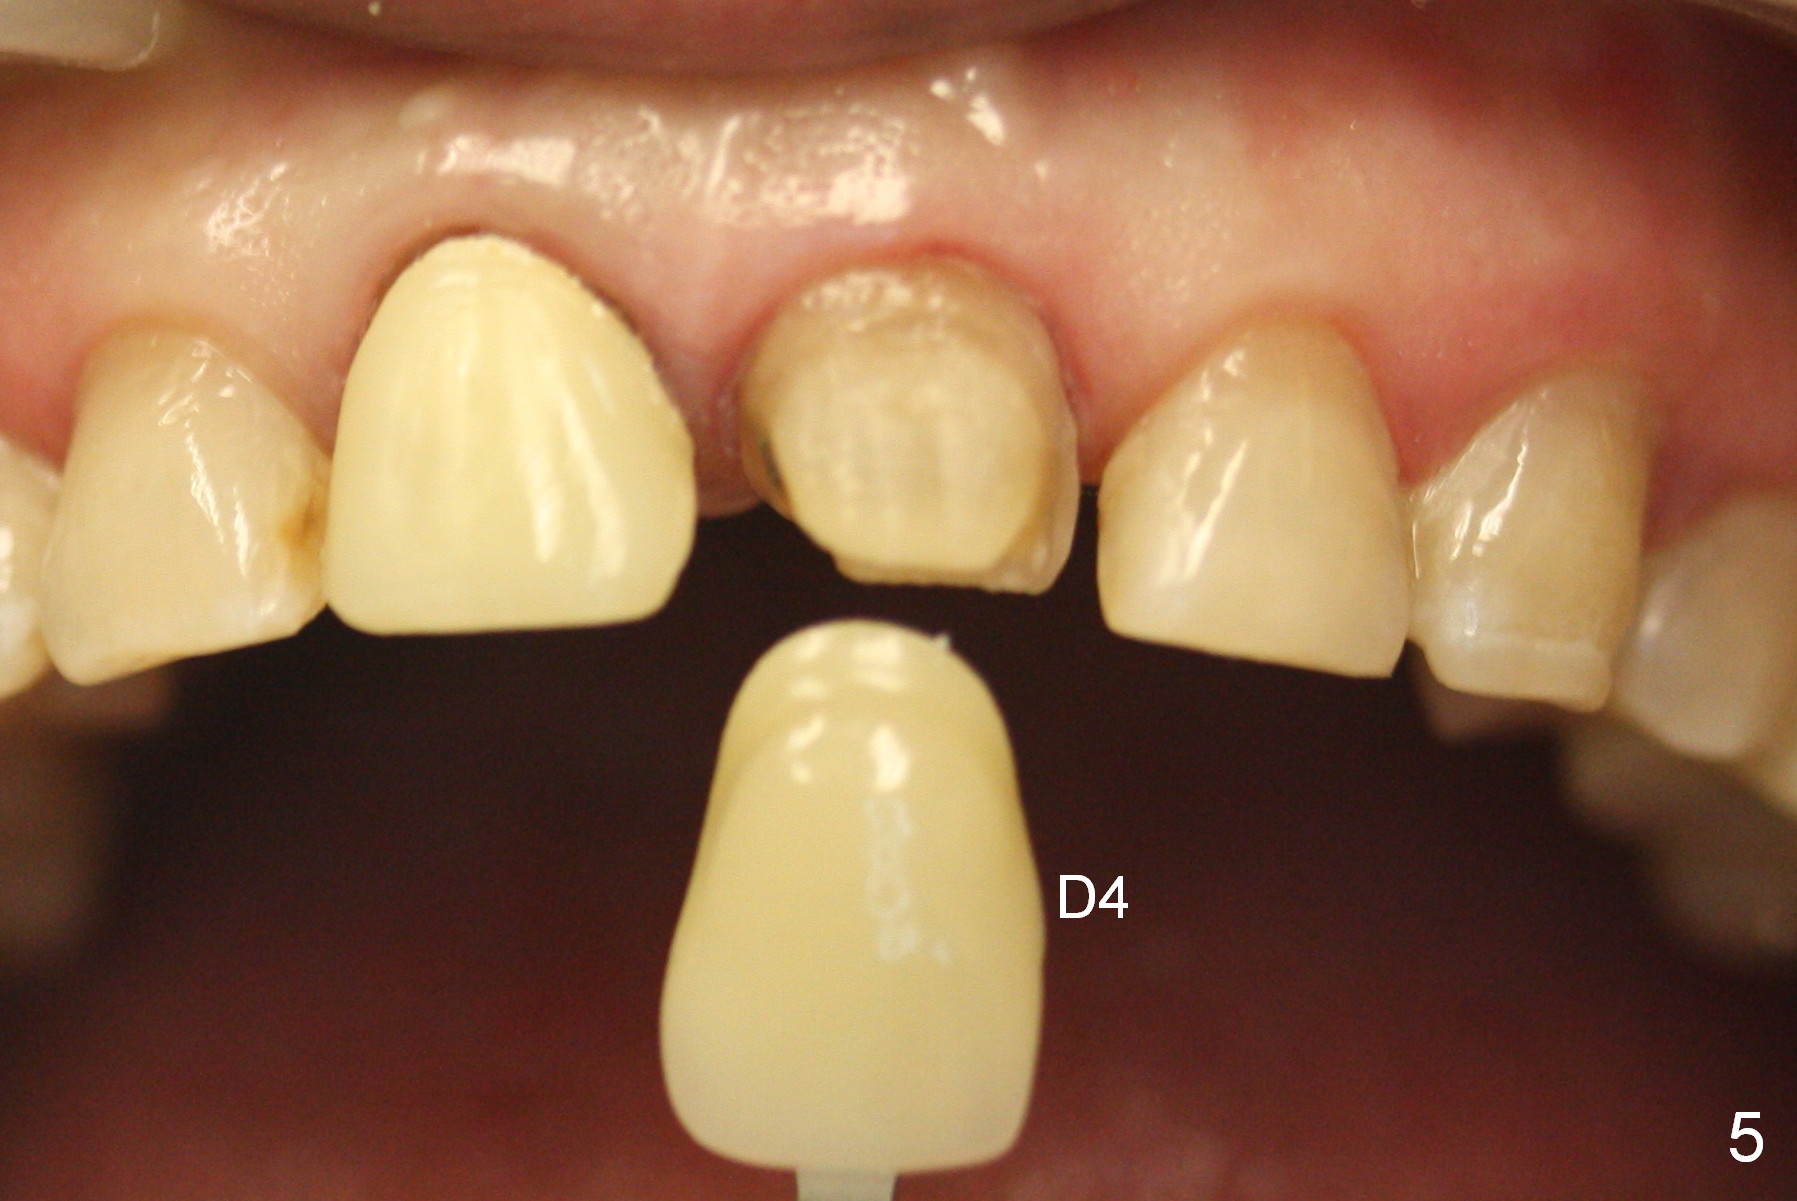

A 54-year-old lady (CL) has a discolored central incisor (#8, Fig.1). Stump shade is shown in Fig.2. Other reference shades are shown in Fig.3-5.